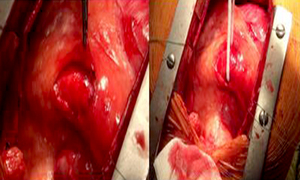

1、外科手术

(1)手术原则:在不影响正常心肌血供的前提下,消除瘘管旁路,并且矫正合并的心脏畸形。

(2)手术方式:目前常用的外科术式有瘘管结扎术、经心腔接口关闭术和冠状动脉切开修补术等。

(3)适应证:适用于解剖结构复杂,异常血管粗大的血管瘘。